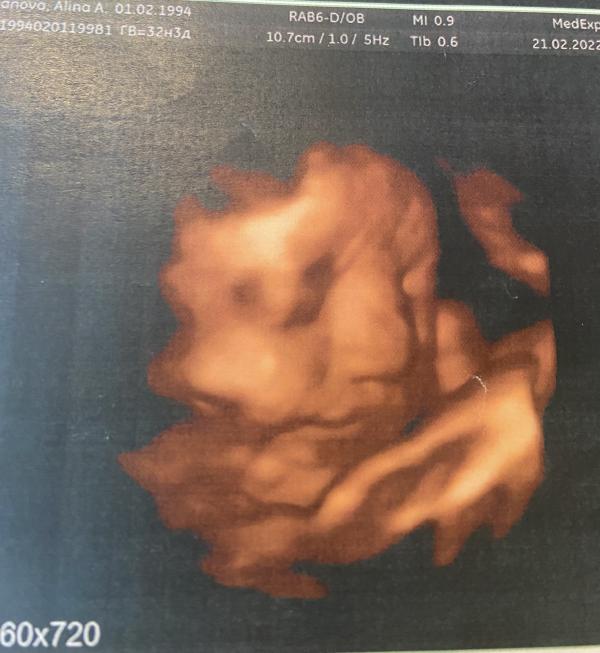

Сегодня с мужем ходили на узи😍Внепланово, чисто для себя)))Господи, сколько эмоций, сколько счастья❤️Наша малышка уже примерно 2 кг😘Наша радость, наше счастье как же мы тебя ждём❤️❤️❤️

Третий скрининг был в 5 жк, где я наблюдаюсь. Впечатлений ни каких, убитый кабинет, допотопная техника, не плохой доктор, но я мне даже ни одним глазом не дали взглянуть на малышку. А сегодня, просто решили с мужем сходить вместе на 3д узи пошли в медэксперт, остались очень довольны хороший доктор, все рассказала, все посмотрела, все показала)))